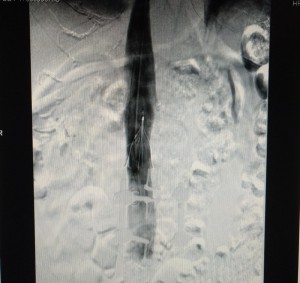

Al observar las dos imágenes con los resultados del Eco-Doppler, podemos destacar trombosis de vena femoral derecha, por lo que para evitar futuros problemas trombóticos, se puso un filtro de vena cava inferior al paciente, para evitar que vuelva a trombosarse el circuito pulmonar.

El filtro de vena cava es un aparato de filtración que se utiliza en aquellos pacientes que, como la de este caso, tienen historia o riesgo de desarrollar trombosis venosa profunda o coágulos en las piernas, para intentar evitar que se cree un émbolo que llegue al corazón o a los pulmones.

Por otro lado, para detectar el origen del émbolo, la más adecuada es la Eco-Doppler, pero en ocasiones puede llegar a emplearse también la flebografía, una técnica más invasiva que permite visualizar las venas de las extremidades inferiores, pelvis y vena cava inferior, pudiendo demostrar defectos de replección u obstrucción vascular. El problema de esta técnica es que es dolorosa, además de producir reacciones locales o sistémicas, y también según el observador hay diferencias de interpretación. Por todo esto, se ha desplazado a favor de la Eco-Doppler, aunque sí que se sigue usando en casos de sospecha de TVP distales a la vena poplítea, o para la visualización de la cava. También, antes de la Eco-Doppler se utilizaban otras técnicas, como la pletismografía de impedancia, sujeta a muchas situaciones que producen falsos positivos.